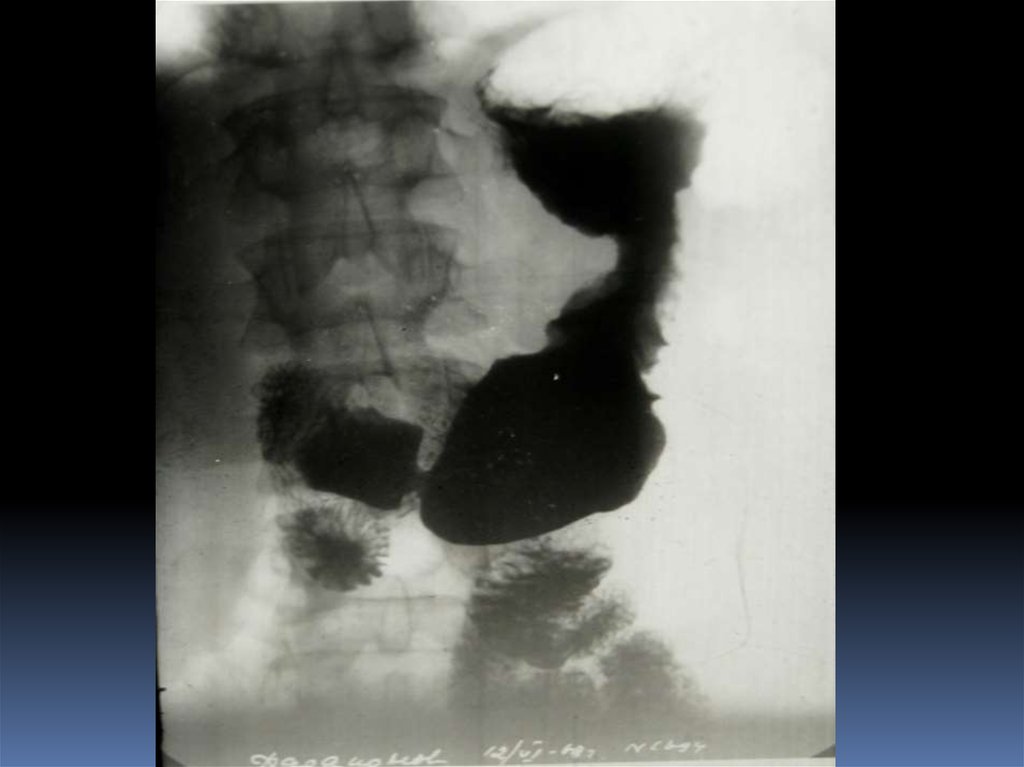

54. Редкие случаи из практики

55.

56.